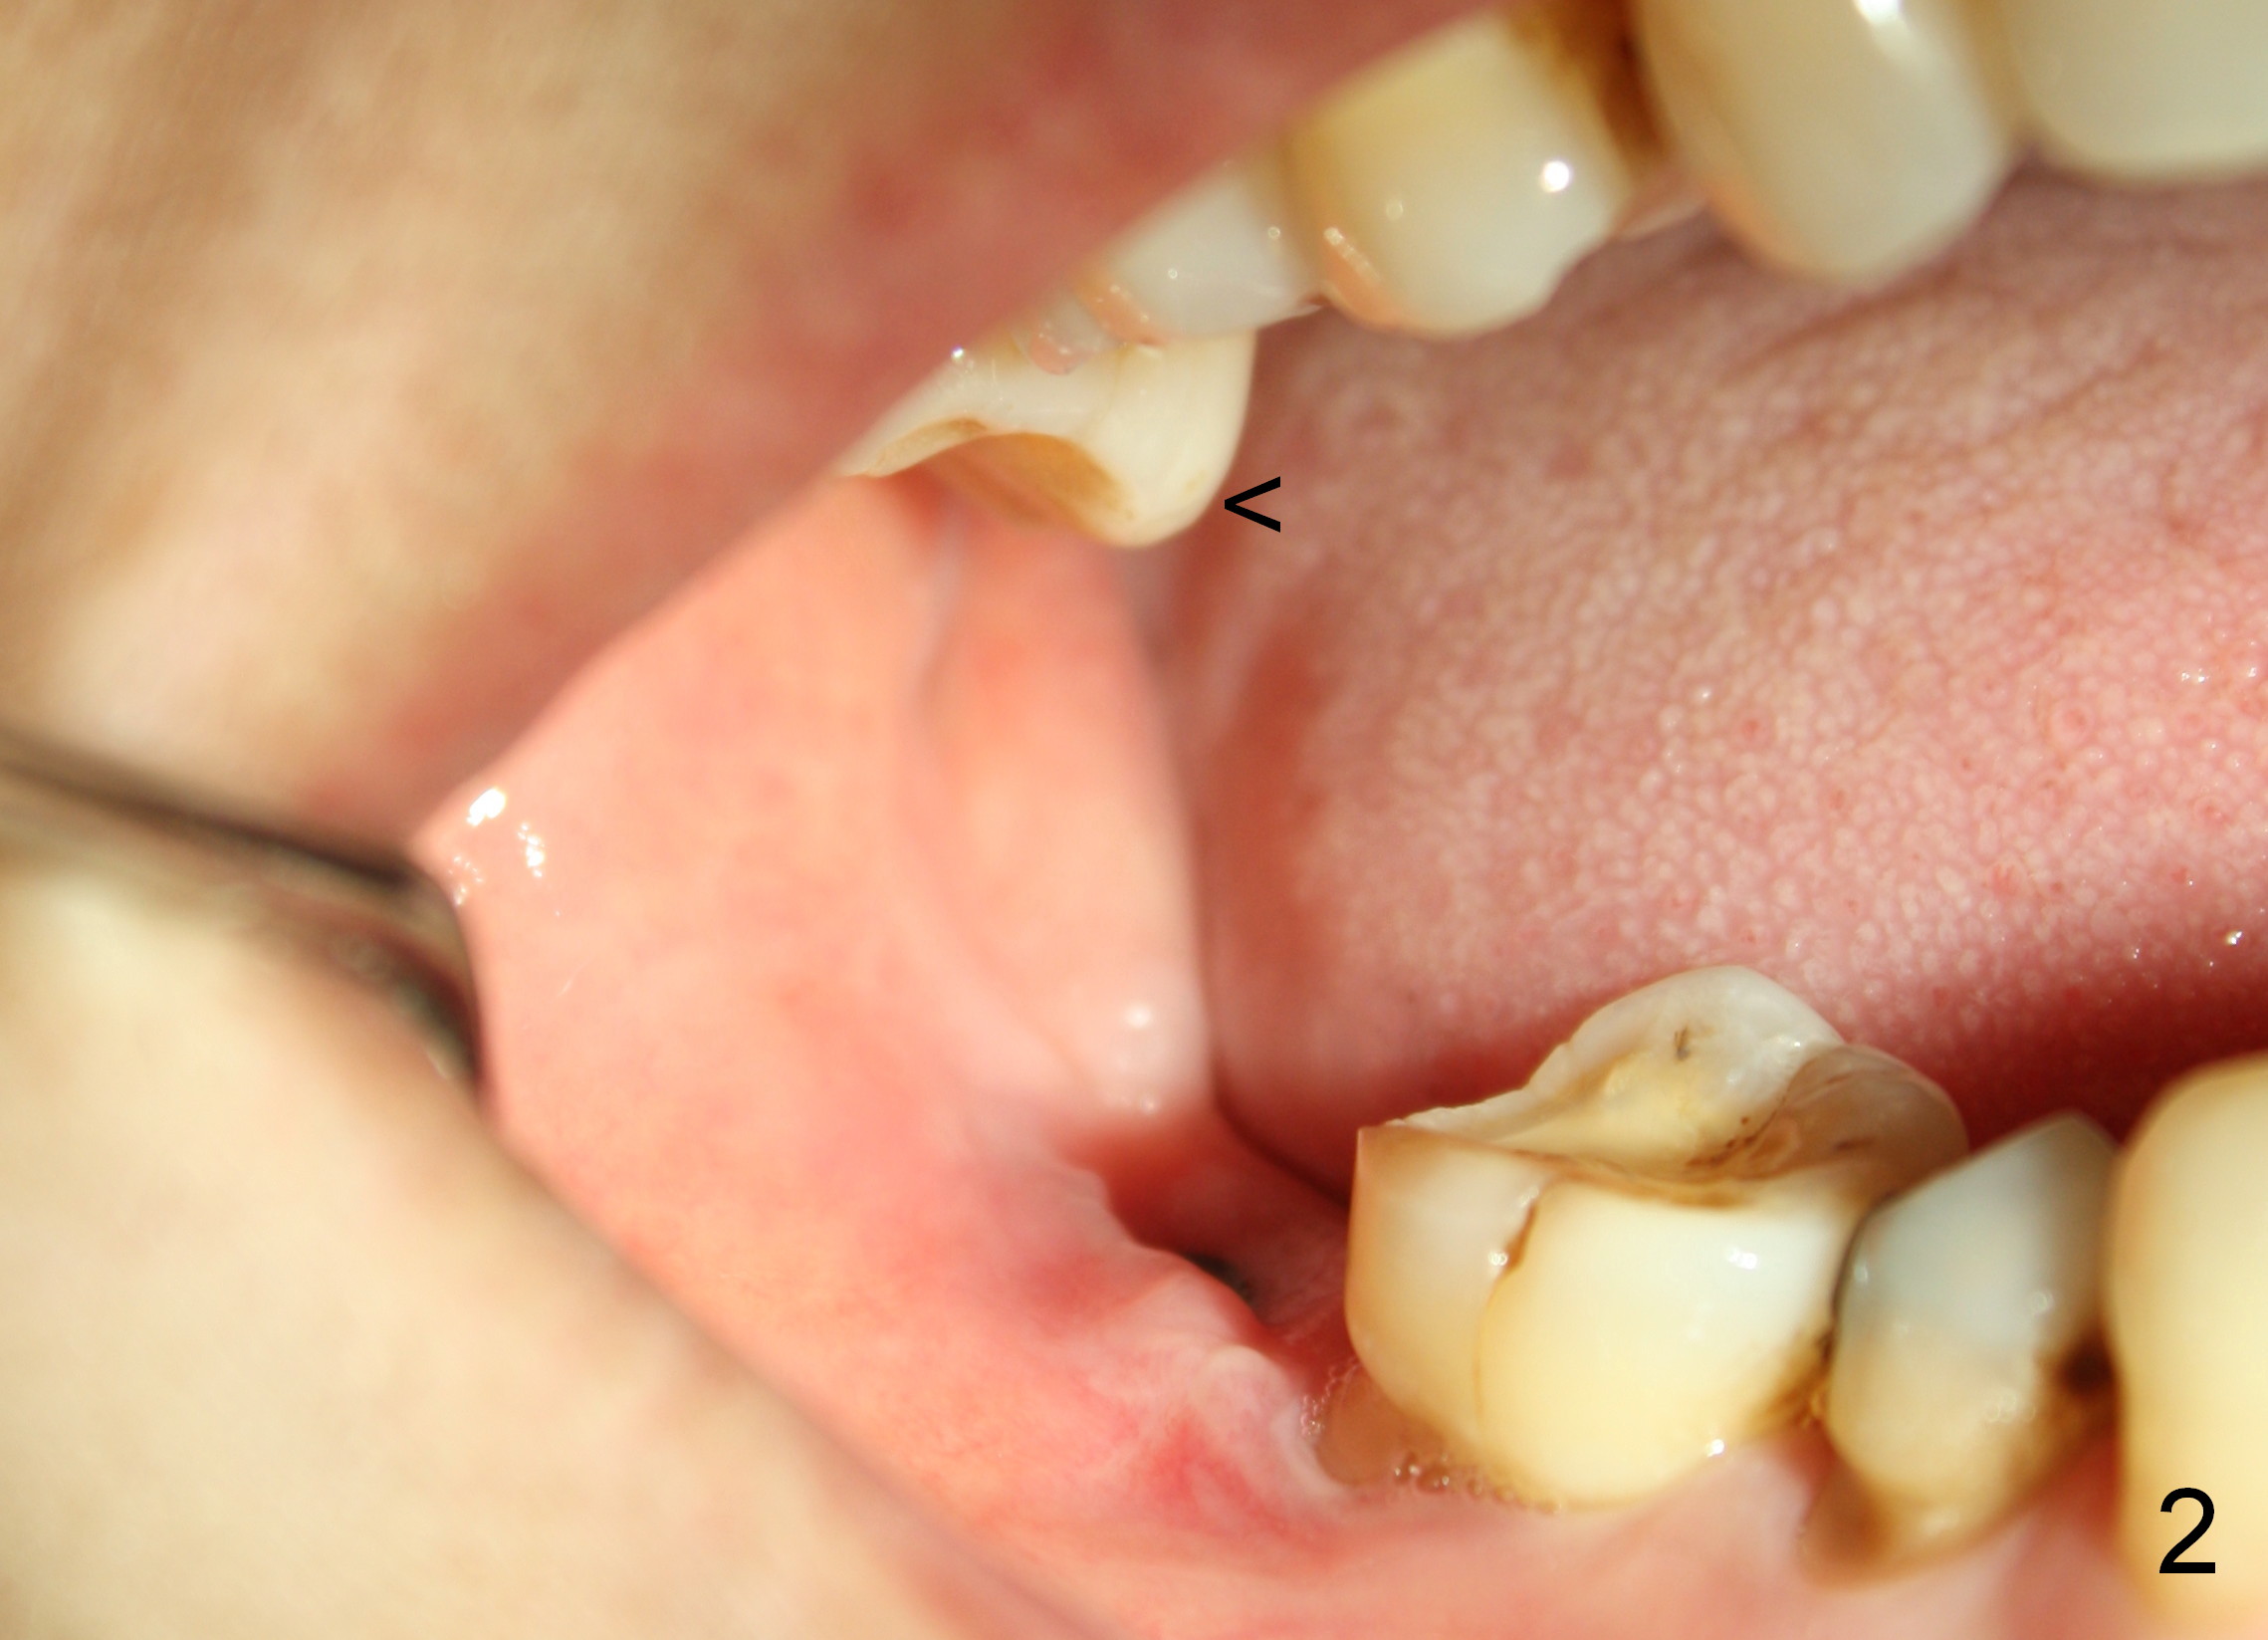

The wound of 2 stage implant surgery is found to be gapping 10 days postop with healing screw exposure 2 weeks postop. Exam at a month postop (Fig.1) shows that the mesiolingual cusp of the upper right 2nd molar is sharp (Fig.2 <) and inserted into the wound of the implant site (Fig.3). Two mini-implants are placed with immediate power chain retraction (Fig.4). The orthodontic intrusion is without effect; brackets are placed 4 months later (Fig.5). Two months later, the patient is diagnosed to have breast cancer. As a precaution for chemotherapy, the orthodontic device is removed. During chemotherapy, the patient returns once. The gingiva around the cover screw is mildly erythematous and edematous. After removing plaque from the cover screw with irrigation, the patient feels a little better. All of the orthodontic appliances are removed before she receives chemotherapy for breast cancer.